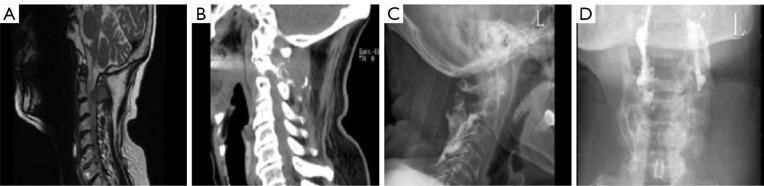

Rare case of recurrent refractory multiple myeloma with lipid deposition in the vertebral body: a case description.